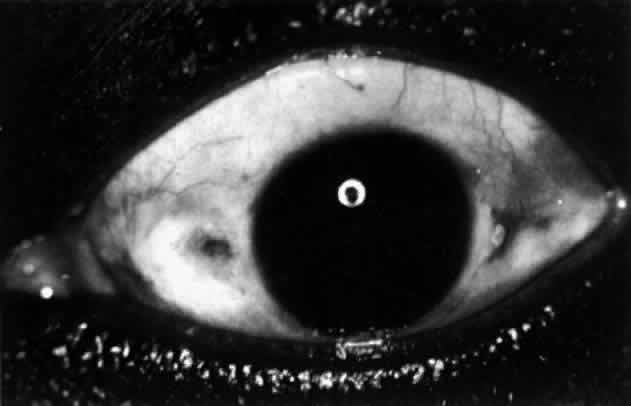

Fig. 28. Nodular scleritis. Both the anterior conjunctival slit and the deep scleral

slit are displaced forward by the scleral edema. There is little

separation between these two beams, indicating that all the edema is in

the sclera and not in the overlying episclera. (Watson PG, Hayreh S, Awdry P: Episcleritis and scleritis. Br J Ophthalmol 52:278–279, 1968) Fig. 28. Nodular scleritis. Both the anterior conjunctival slit and the deep scleral

slit are displaced forward by the scleral edema. There is little

separation between these two beams, indicating that all the edema is in

the sclera and not in the overlying episclera. (Watson PG, Hayreh S, Awdry P: Episcleritis and scleritis. Br J Ophthalmol 52:278–279, 1968)

|